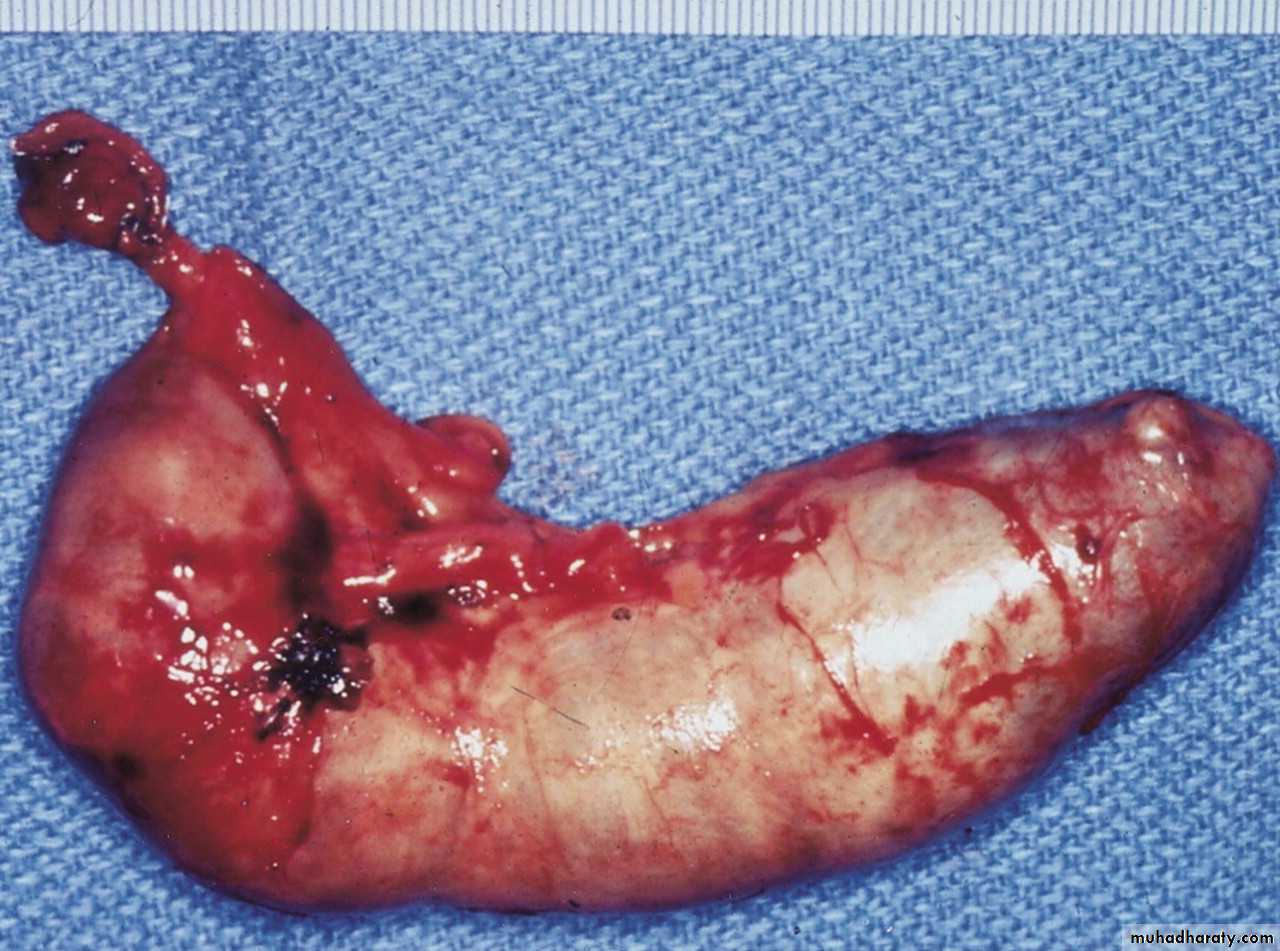

. If the condition progresses further distension of the appendix may cause venous obstruction and ischemia of the appendicular wall. With ischemia, bacterial invasion occurs through the muscularis properia and submucosa producing acute appendicitis, with free contamination to peritoneal cavity. Alternatively, the greater omentum and loops of small bowels becomes adherent to the inflamed appendix , walling off the spread of peritoneal contamination and resulting in a phlegmonous mass or paracecal abscess. Rarely appendicecal inflammation resolves , leaving a distended mucus-filled organ termed a mucocele of the appendix.

Peritonitis is a bad complication of acute appendicitis and to be as result of free migration of bacteria through an ischemic appendicular wall or from frank perforation or gangrenous appendix or from delayed perforation of appendicular abscess. Factors that may play a role in perforation and peritonitis are extremes of age, immunosuppression, diabetes and fecolith obstruction of the appendix lumen, a free-lying pelvic appendix and previous abdominal surgery that limits the ability of the greater omentum to wall off the spread of peritoneal contamination. At this case a rapid deteriorating clinical course is accompanied by signs of diffuse peritonitis and systemic sepsis syndrome called septic shock.

The elderly: gangrene and perforation occur more frequently in elderly patients. Elderly patients with lax abdominal wall or obesity may harbor a gangrenous appendix with little evidence of it and the picture may simulate sub acute intestinal obstruction. These features coupled with coincident medical conditions produce a much higher mortality for acute appendicitis in the elderly.